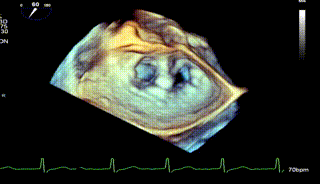

术前TEE评估

术前瓣膜介入团队的心超医生陈星星医师王良国医师对患者的心脏结构和瓣膜解剖情况进行详细的评估:

1.二尖瓣重度关闭不全(4+),瓣环明显扩大(AP径4.6cm,LM径3.9cm),扁平,关闭时瓣叶对合不佳(carpentier I),1-3区均可见反流束,返流宽度达26mm;肺静脉频谱呈收缩期反向。

2.画迹法测得二尖瓣瓣口面积约8.8cm²。

3.PISA法测得EROA=0.57cm²,Rvol=77ml,r=11mm。

4.二尖瓣前叶(A2)长度29mm,后叶(P2)长度11mm。

5.左房巨大(三径86*84*114mm),右房巨大(内径114*86mm),CFI提示极重度三尖瓣反流,Teich法测得EF为70.1%。

怎么上穿刺鞘攻克巨大左房伴转位穿刺难关!温医大附一院周浩教授团队创新应用“导丝定位+可调弯鞘”技术完成高难度TEER手术_https://www.jmylbn.com_新闻资讯_第2张

1区带彩

2区带彩

3区带彩

3D带彩

术前肺静脉频谱